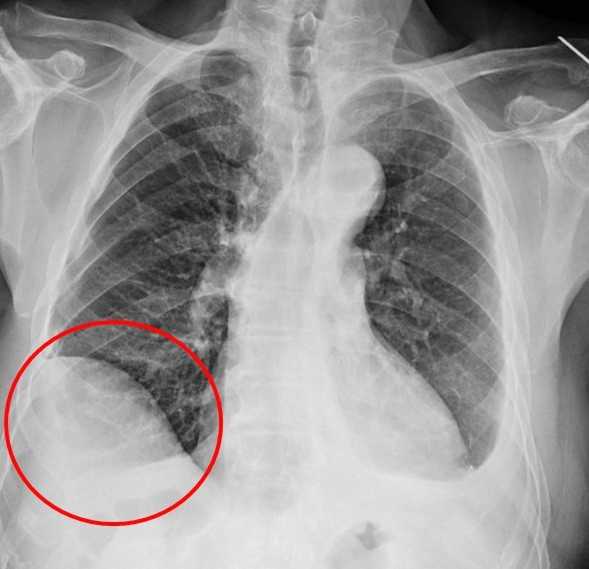

【記者 陳文偉 台中報導】75歲吳先生因肝臟細胞癌在仁愛長庚合作聯盟醫院(大里仁愛醫院)接受治療,期間發現右下肺有一顆約1.2公分新發現的腫瘤,因疑似肺癌故轉介到胸腔及心臟血管外科廖啟耀主任門診,經醫療團隊和家屬討論後決定做手術切除該腫瘤。由於病人過去有車禍導致橫隔膜受傷的病史,所以讓手術預期難度相對提高,經採用達文西機器人手術系統執行肺節切除手術,並且順利地於術後第三天出院返家休養。

廖啟耀主任表示,雖然肺臟腫瘤手術在台灣十分普及且發達,但是有些病人的情況會使醫師預期手術難度提高,其中以過去有過外傷經歷、曾經接受過胸腔手術、肺臟腫瘤接受過放射性治療的病人最為常見,這類病人常見的手術困難度為解剖構造的改變,常因為胸腔發炎反應的影響,讓肺臟與周遭肋膜產生沾黏,同時血管的方向也更難分辨,對執行手術醫師而言是一項困難的挑戰。

廖啟耀主任指出,仁愛與長庚醫療體系聯盟醫院近年來積極引進達文西機器人手術系統,並成立微創暨達文西手術中心,致力推動高品質、低侵襲性的手術照護。手術中病人的橫隔膜如果符合預期和肺臟沾黏,因此手術空間也較為狹小,達文西機器人手術可提供穩定的操作及清晰的手術視野,這對於外科醫師在分沾黏上是如虎添翼。達文西手術在這方面優勢更顯得突出,透過穩定且精細的操作,團隊將吳先生的橫隔膜與肺臟分離,並完成之後的肺節切除手術。

雖然因為外傷病史使手術困難度上升,廖啟耀主任的團隊藉由達文西機器人手臂幫助下成功完成手術,過往使用傳統開胸手術或胸腔鏡手術於類似的病人,常因為分沾黏導致肺破損所以需要較長的恢復時間,但是在進行達文西手術的過程中,不只術中沒有發生因為分沾黏常見的出血、肺破損等問題,吳先生在術後第二天便可拔除胸腔引流管,恢復順利。